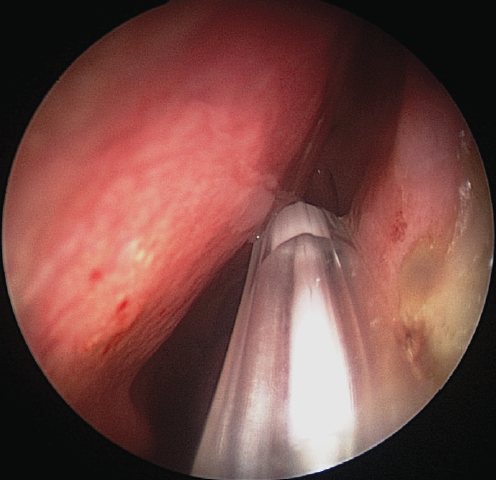

Fig. 4. Endoscopic view of a left nasal cavity with an inserted and inflated balloon catheter

Рис. 4. Эндоскопическая картина полости носа (левая половина носа) с введённым и раздутым баллонным катетером

The intervention was performed as follows. Under local and conduction anesthesia with intravenous sedation, antegrade probing of the dacryostomy area was performed with the formation of an opening in the scar tissue (in three cases) and with probing of residual dacryostomy (in three cases; Fig. 2). Purulent discharge was removed from the lacrimal sac cavity using an aspirator. A balloon was inserted endonasally into the dacryostomy opening using a curved von Eicken cannula for irrigation with an outer diameter of 4.0 mm and length of 15 cm (Karl Storz, Germany; Fig. 3). Balloon dacryoplasty was performed according to the protocol we developed earlier in the experiment [8] and tested in the clinical setting (Fig. 4) [9]. The balloon was dilated at a pressure of 8 atm. for 90 s, and after 10 s, it was repeated for 60 s. After deflation, the balloon was removed. Figure 5 shows an enlarged dacryostomy after the intervention. A hemostatic sponge was inserted into the dacryostomy area, which was removed 48 h after the surgery.